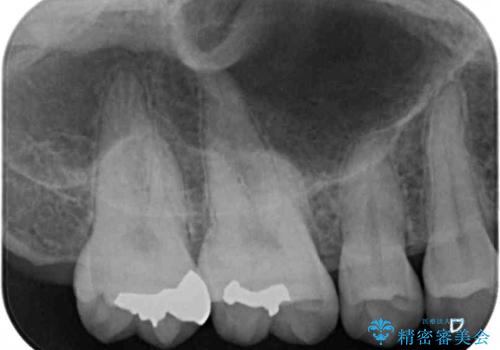

- 奥歯の銀歯と虫歯を気にして来院された患者様です。

下顎は口を開けたときに目立つためセラミックインレーに、上顎奥歯は機能面を優先してゴールドインレーにて修復治療を行うこととしました。

機能面を優先すると、PGAインレー(ゴールドインレー)による修復治療やPGAクラウンによる補綴治療が望ましいのですが、笑ったときに見えている銀歯がどうしても気なってしまうとのことで、目立ってしまう奥歯はセラミックインレーやセラミッククラウンを装着することとしました。

見た目を気にすることなくむし歯治療を行うことができ、患者様に大変満足していただきました。